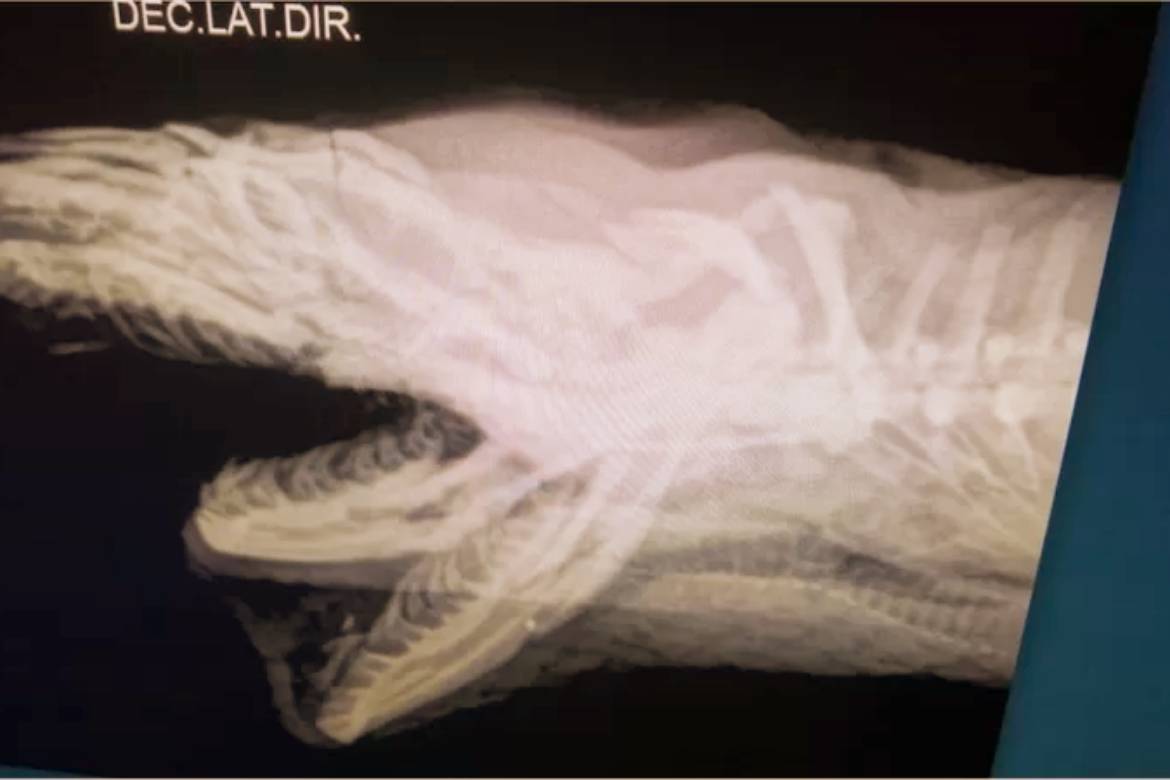

Segundo o diretor do Vida Livre, Roched Seba, a serpente chegou com diversas fraturas e ferimentos na cabeça e em estado grave.

Ela foi medicada para reduzir sua dor extrema e os danos do ferimento, estabilizada e seguiu para uma rotina de exames radiograficos, para a posterior imobilização de sua mandíbula.

Ela também teve sua cabeça e mandíbula imobilizadas. Tratamentos alternativos que ajudam na cicatrização e reversão dos processos inflamatórios como o laser e a moxaterapia (técnica de acupuntura com calor), também foram usados.